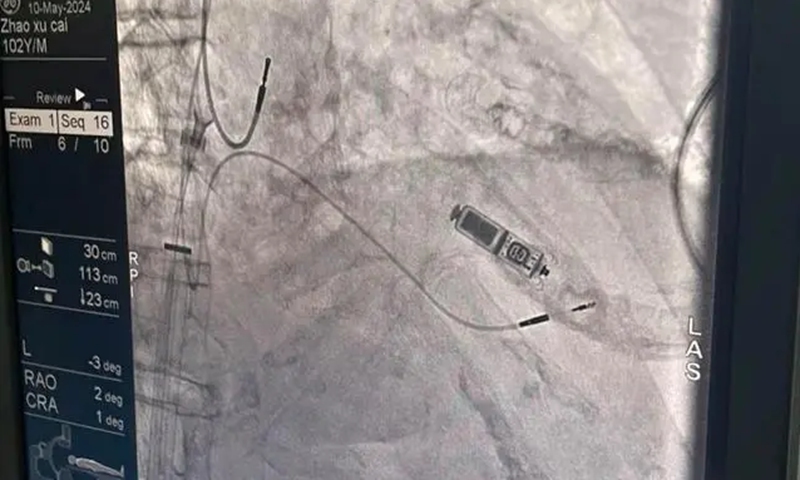

ECG monitoring shows a restored normal heart rhythm of Zhao Photo:screenshot from Hunan local media outlet

The innovative "capsule pacemaker" is the size of a capsule, weighing less than 2 grams, which does not require wires or incisions in the skin, minimizing the risk of infection.

Under local anesthesia, the pacemaker was implanted into Zhao's right ventricular septum through his femoral vein, providing the necessary cardiac pacing function without the complications associated with traditional pacemakers.

Following a detailed anesthesia assessment and precise planning by anaesthetist Zeng Guang and his team, the pacemaker was successfully implanted in Zhao's optimal pacing site.

Post-surgery, continuous cardiac monitoring showed a restored normal heart rhythm, alleviating the life-threatening condition and allowing Zhao to transition to the ward for further treatment.